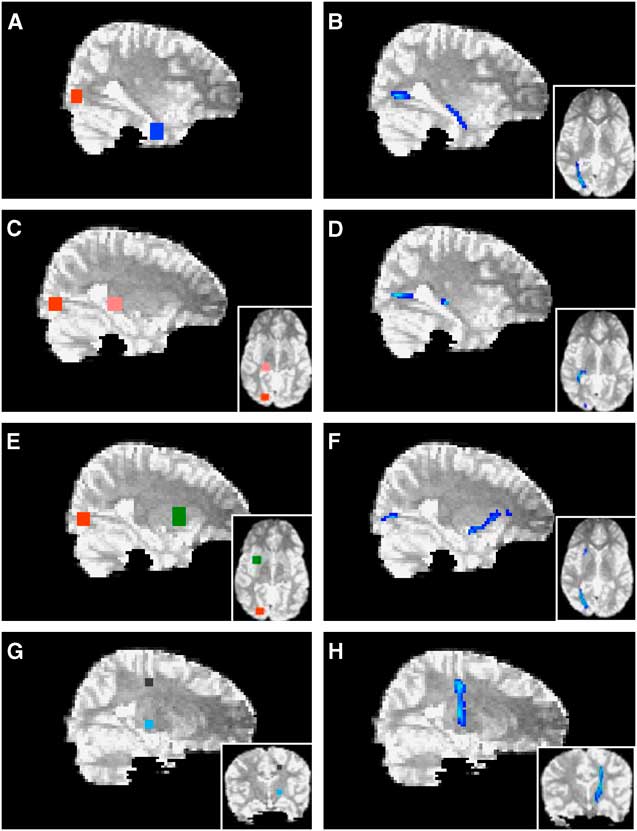

Probabilistic tractography was performed using Probtrackx (Behrens et al., Reference Behrens, Johansen-Berg, Woolrich, Smith, Wheeler-Kingshott, Boulby and Matthews2003) to delineate tracts and pathways. The cortico-spinal tracts were seeded from a region of interest (ROI) determined by MEG localization of the motor field. Represented as a 9-voxel cluster, peak activity of finger movement from MEG was localized on the T1 image (0.9375 mm slices) and served as a reference for seeding cortico-spinal tracts. This cluster was expanded across four slices in the Z-axis to create a volume large enough to accommodate reconstruction following registration to the lower resolution DTI space (2.5 mm slices). As MEG activations were localized within cortical grey matter, representative ROIs for tract-seeding were drawn in the nearest adjacent white matter orthogonal to the main axis of the respective gyrus. The volume was then non-linearly registered to the b = 0 image of the DTI sequence (Woods, Grafton, Watson, Sicotte, & Mazziotta, Reference Woods, Grafton, Watson, Sicotte and Mazziotta1998). The cortico-spinal tracts were then launched from a seed comprised of 27 voxels across two slices and tracked via the posterior arm of the interior capsule. Anatomical landmarks were used as seeds and waypoints for all other tracts and pathways (Figure 3). ROIs were drawn directly on the b = 0 image as 6 × 6-voxel clusters across five slices (total volume = 395 mm3). The lateral geniculate nucleus was used as a seed to delineate the optic radiations with a termination seed at the calcarine fissure. The calcarine fissure was used as a seed to delineate both the inferior fronto-occipital fasciculus and the inferior longitudinal fasciculus via the external capsule and temporal lobe white matter, respectively. All tracts and pathways were thresholded to eliminate non-robust probabilities by removing voxels within the lowest 10%. Quantitative measures (FA, MD, AD, and RD) were then extracted across each delineated tract or pathway.

Fig. 3 Probabilistic tractography. The calcarine fissure (red in A, E) was used as a seed to delineate both the inferior longitudinal fasciculus (B) and the inferior fronto-occipital fasciculus (F) via temporal lobe white matter (blue in A) and the external capsule (green in E), respectively. The lateral geniculate nucleus (pink in C) was used as a seed to delineate the optic radiations (D) with a termination seed at the calcarine fissure (red in C). The cortico-spinal tracts (H) were launched from an MEG-derived seed (black in G) and tracked via the posterior arm of the interior capsule (light blue in G). Axial views are depicted in insets.